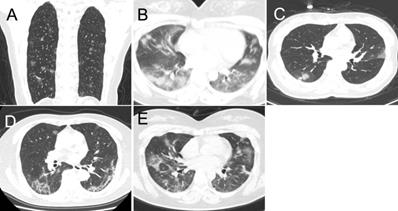

Figure 1

The predominant CT patterns of mild COVID-19 pneumonia. A. GGO. B. Consolidation. C. GGO and consolidation. D. Linear opacity. E. Linear opacity, GGO and consolidation.

Demographic data, epidemic-related factors, symptoms, underlying medical conditions, laboratory tests, and date of admission and discharge were collected from electronic medical records. If we encounter uncertain patients, we have confirmed the information via telephone or directly to communicate with each other. The CT images were evaluated by two radiologists with 15 and 10 years of experience in chest imaging; disagreements were resolved by consensus. All CT imaging features were defined according to the Fleischner Society Glossary of Terms in Thoracic Imaging as well as peer-reviewed literature on viral pneumonia [17, 22-24]. The following imaging features were reviewed for all patients (the definition of CT was attached as a supplementary file ): lung involvement, extent of lesion involvement, predominant location, margin definition, lung segments of lesion distribution, number of lung segments and lobes involved, predominant CT pattern (Figure 1), and the presence of pure ground glass opacity (GGO), pure consolidation, GGO with consolidation, linear opacity, crazy-paving pattern, air bronchogram, reversed halo sign, nodules, thickening of the adjacent pleura, pleural effusion, thoracic lymphadenopathy, emphysema, round cystic changes, calcification, cavitation, bronchiectasis, and honeycomb pattern. A pre-established severity scoring system was applied [24]. Each lung was divided into upper, lower, and middle zones demarcated as above the carina, below the inferior pulmonary vein, and between these, respectively (total of six lung zones). Scores for each zone were defined as follows: score 0, 0% involvement; score 1, less than 25% involvement; score 2, 25% to less than 50% involvement; score 3, 50% to less than 75% involvement; and score 4, 75% or greater involvement. Total scores were the sums of the six zones (range of possible scores, 0-24). In addition to total lesions score, we evaluated the individual total scores for GGO, consolidation, and linear opacity in all lesions. To obtain detailed information about the dynamic evolution of CT features with disease progression, we divided the time axis into four stages according to the interquartile range of the time from the onset of illness: stage 1 (1-6 days), stage 2 (7-13 days), stage 3 (14-22 days) and stage 4 (>22 days).